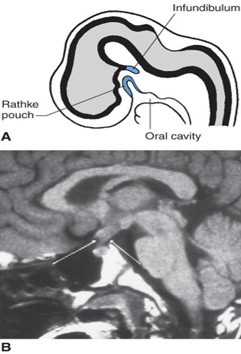

2. Hypophysis (pituitary gland) is attached to the hypothalamus by the pituitary stalk and consists of the anterior lobe (adenohypophysis) and the posterior lobe (neurohypophysis).

1. Anterior lobe (adenohypophysis) develops from Rathke’s pouch, which is an ectodermal diverticulum of the primitive oral cavity (stomodeum). The diagram (Figure 17.17A) shows a midsagittal view of an embryo at week 6 indicating Rathke’s pouch and the infundibulum. Remnants of Rathke pouch may give rise to a craniopharyngioma. A craniopharyngioma is the most common supratentorial tumor occurring in childhood and is the most common cause of hypopituitarism in children. The MRI (Figure 7.17B) shows a craniopharyngioma (arrows), which lies suprasellar in the midline, compressing the optic chiasm and hypothalamus.

1. Posterior lobe (neurohypophysis) develops from the infundibulum, which is a neuroectodermal ventral evagination of the hypothalamus.